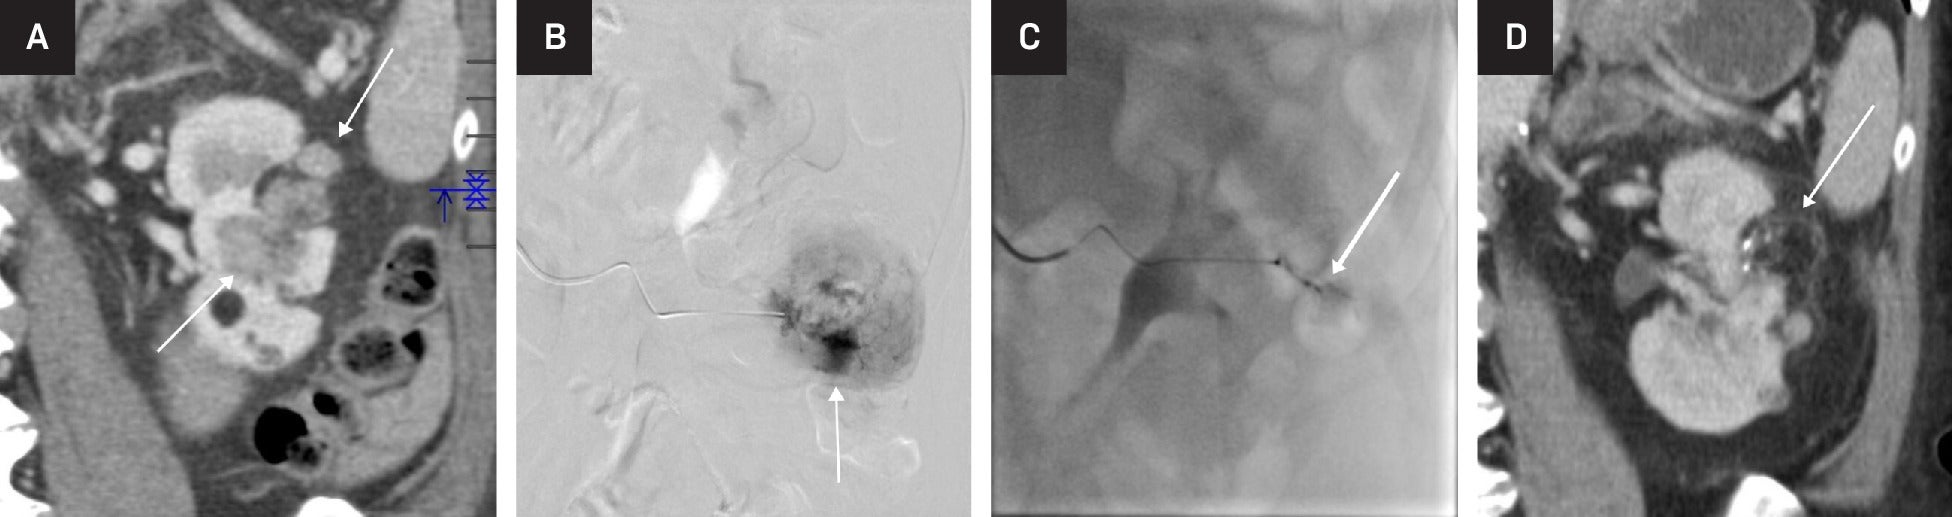

Embolization of large angiomyolipoma (AML). Coronal reformation contrast-enhanced CT showing AML with a large solid component (arrows) (A). Selective catheter angiography showing pooling of contrast (arrow) within the AML (B). Post-embolization catheter angiography showing near-complete occlusion of the vascular component of the AML (arrow) (C). Follow-up coronal reformation contrast-enhanced CT showing regression of the solid component of the AML, with some of the fatty component still visible (arrow) (D).

Arterial embolization and lesion ablation are common radiological interventions for AMLs. Embolization is preferred for larger tumors as it more effectively and directly addresses their vascular components. Arterial embolization may be used for prophylactic treatment of tumors >4 or >6 cm or those with aneurysms, and it is the treatment of choice when there is associated hemorrhage. Embolization is minimally invasive, with minimal blood loss and short hospital stay compared with surgical intervention.16